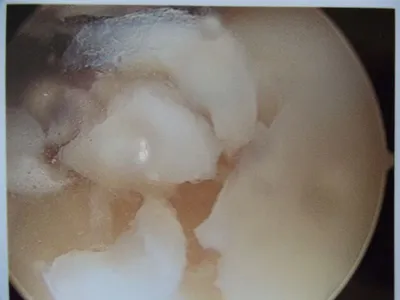

A series of intraop ankle arthroscopy pics of synovial chondromatosis with OCD talus and tibia and microfracture.

Pic of one of the nodules inside the ankle joint.